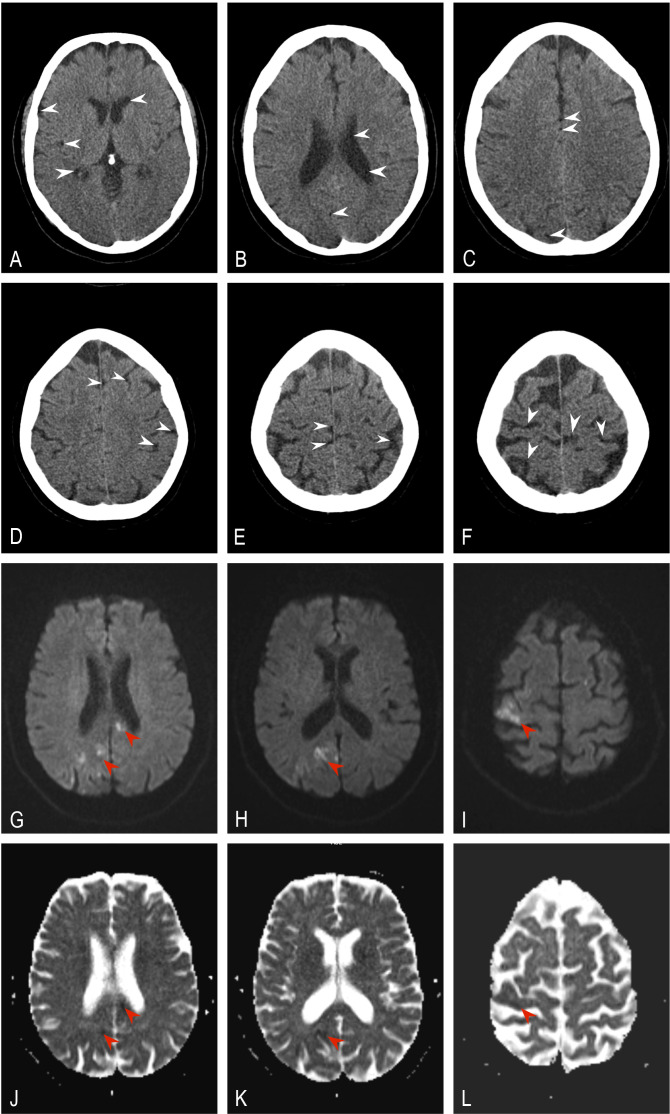

Case presentation: We present a case of a 58-year-old woman with acute onset limb weakness and speech disturbance that happened during a lumbar intradiscal oxygen-ozone injection session. Brain CT and MRI scans showed multiple cerebral gas embolisms and diffusion-restricted areas in both cerebral hemispheres. Echocardiography revealed a patent foramen ovale, hinting at a conduit for paradoxical embolism. Follow-up of the patient after 1 year showed significant improvement.